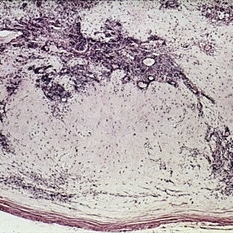

Microphthalmos with cyst. Left side shows the macroscopic appearance and right side the microscopic appearance, of a microphthalmic eye with continuou cyst. The eye has multiple anomalies such as hypoplasia of the iris, cataract, nonattachment of the retina, and retinal dysplasia (right, H&E x 1).

Condition/keywords: cataract, cyst, dysplasia, hypoplasia, microphthalmos